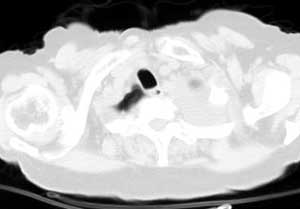

从图片看,包裹性积液好象更合理,梭形,ct值3-5hu(在哪看到的?);胸膜间皮瘤如此规则,不多见。

左侧背部胸膜肥厚,伴包裹性积液,不考虑间皮瘤.

同意以上各位的高见,首先考虑包裹性积液,1.胸膜间皮瘤积液量一般较大,以游离性积液更为常见,2.可以看到增厚的胸膜结节